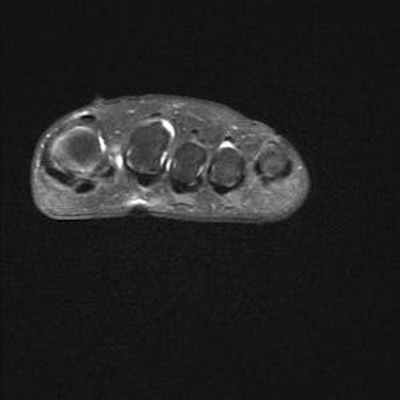

Боль в переднем отделе стопы правой ноги у пациентки 19 лет, в области головки 2-ой плюсневой кости.

Головка 2-ой плюсневой кости выглядит сплюснутой и расширенной с правой стороны в связи с болезнью Фрейберга.

Отсутствие внутрикостной отёчной инфильтрации по краям суставной щели плюснефалангового сустава. Напротив, следует отметить наличие внутрисуставного выпота.

Отсутствие бурсита между головками плюсневых костей или под ними.

Не обнаружено невромы Мортона или тендовагинита.